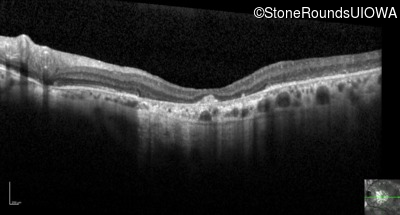

Optical Coherence Tomography - Right - 20/125 -2

Exemplar / OCT Stack